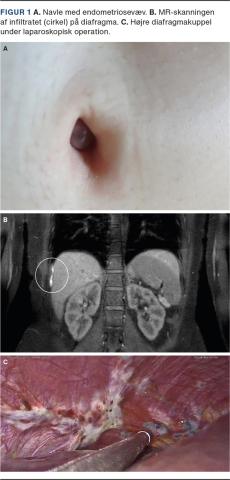

En 27-årig kvinde blev henvist fra egen læge til en kirurgisk afdeling pga. en tumor i umbilicus. Efter ophørt brug af p-piller havde hun i forbindelse med menstruation smerter, blålig hævelse og blødning fra umbilicus (Figur 1A).

På baggrund af kvindens cykliske smerteproblematik i højresidige øvre abdomen foretog man MR-skanning, som viste et ca. 4 cm stort endometriosesuspekt infiltrat på højre diafragmakuppel (Figur 1B).

På højre diafragmakuppel fandt man udbredte endometrioseforandringer (Figur 1C), som blev fjernet med et kirurgisk instrument baseret på argongas. I samme seance blev umbilicus rekonstrueret.